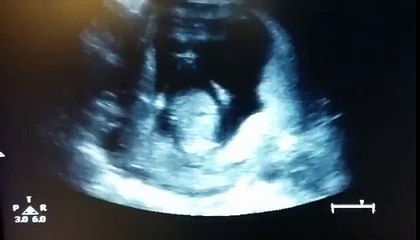

Cuándo se indica una ecografía o una mamografía